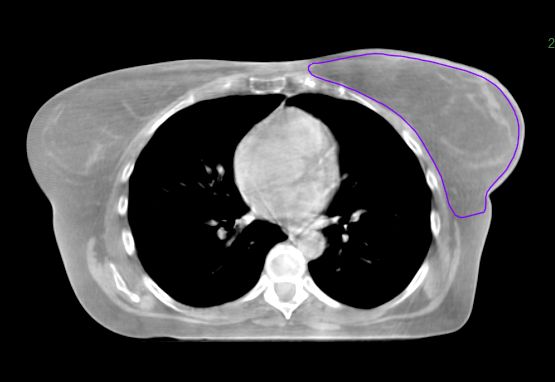

Breast

This HyperSight cone-beam CT for planning (CBCTp*) image, taken using a Varian Halcyon system,** encompasses the entire breast and body, giving clinicians the information they need to generate the initial treatment plan. During treatment, the larger FOV also enables clinicians to see and assess changes in adjacent anatomical structures and landmarks. If the change is deemed significant enough that offline adaptive is needed, they may be able to replan using the latest HyperSight CBCT image.

*CBCTp is an image-only workflow only available on the Halcyon system.

**HyperSight on Halcyon has different specifications than HyperSight on TrueBeam, as the system configuration for Halcyon allows for a larger kV imaging panel.